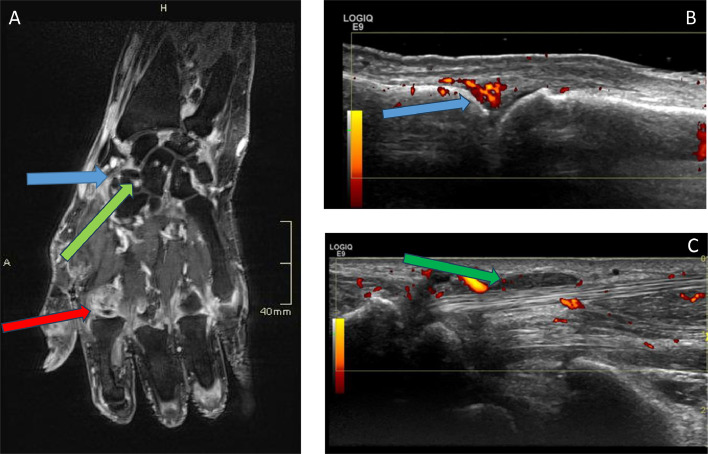

Immune checkpoint inhibitors (ICI) used for the treatment of malignancy are associated with immune-related adverse events, which include inflammatory arthritis. ICI-induced inflammatory arthritis (ICI-IA) is a new clinical entity that may lead to functional impairment and may be persistent even after ICI cessation. We discuss the clinical features, investigation and differential diagnosis. Management needs to consider the safety of immunosuppression in the context of the underlying cancer, and current practice will be further informed by ongoing clinical trials.